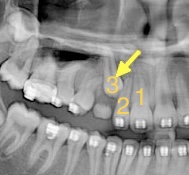

矯正歯科では、

CTスキャンは肉眼で確認できない、

生えないまま骨内に埋もれている歯(埋伏歯)の発見と、

その歯の詳細把握に役に立ちます。

埋伏歯は

下記の写真の3番目の歯ように

表に出てきておらず

埋まっています。